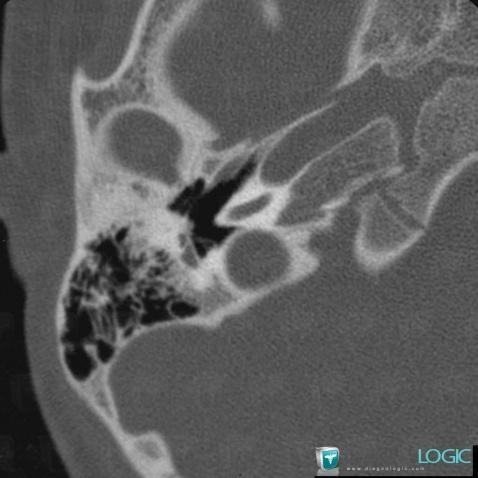

Major aplasia, Middle ear, CT

Here is the specific information in the key image above:

- Diagnosis Major aplasia, Location(s) Middle ear, with gamuts

Major aplasia, External ear, CT

- Diagnosis Major aplasia, Location(s) External ear, with gamuts External ear lesion